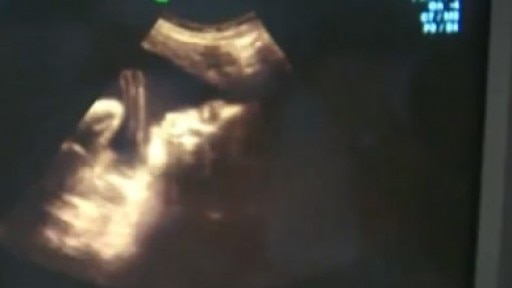

Controversial Texas fetal tissue rules go into effect Dec. 19th

The Texas Department of State Health Services says two public hearings and 35,000 comments were taken into consideration as they finalized the latest abortion rules in the state.